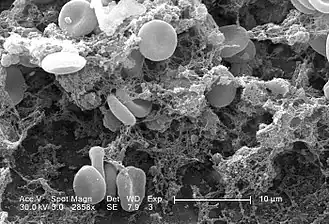

La coagulation intravasculaire disséminée (CIVD), aussi appelée syndrome de défibrination ou coagulopathie de consommation, est une activation pathologique de la coagulation (formation de caillots sanguins). Elle apparaît dans de nombreuses situations pathologiques quand de petits caillots se forment dans les vaisseaux sanguins de tout l'organisme[1]. Ces caillots consomment les facteurs de coagulation. La coagulation normale est ainsi empêchée et des hémorragies (saignements) anormales apparaissent sur la peau (notamment aux sites de prélèvements sanguins), le tube digestif, le tractus respiratoire et les cicatrices chirurgicales. Les petits caillots perturbent aussi le flux sanguin vers les organes (comme les reins) et entraînent une perturbation de leur fonctionnement[2].

- associés à un syndrome hémorragique par consommation non régulée de tous les facteurs de coagulation de la voie extrinsèque (II, V, VII, VIII, X, fibrinogène) ainsi que des plaquettes circulantes ;

- troubles de l'hémostase primaire et secondaire : un allongement du temps de céphaline activée et une diminution du taux de prothrombine (ou allongement du temps de Quick) ;

- un déficit en facteur de coagulation (diminution du fibrinogène, des facteurs II, V, VII, et VIII, X), et une thrombopénie ;

- transfusion plaquettaire, afin de maintenir son niveau de manière satisfaisante ;

- transfusion de culots globulaires en cas d'anémie associée.